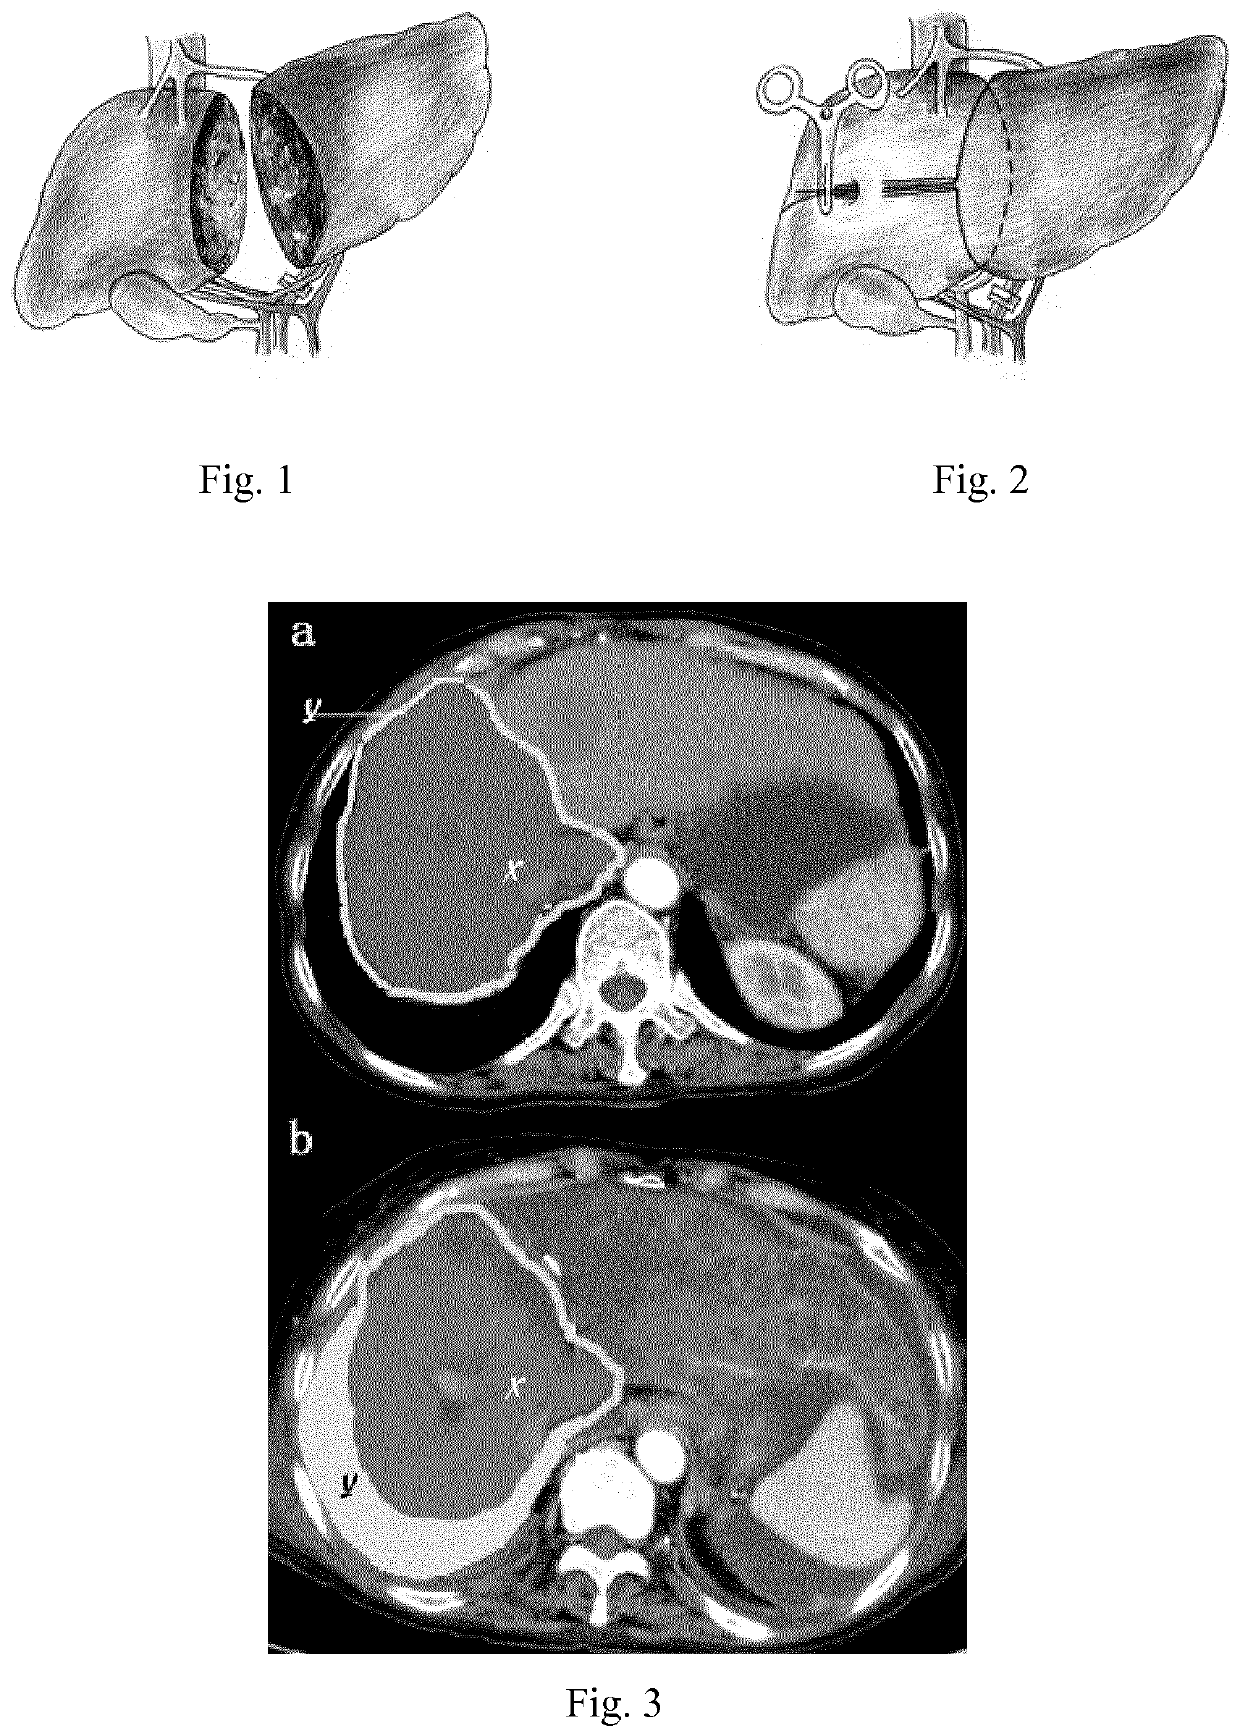

Total laparoscopic two-stage surgical method for resection of side of liver of patient via liver-surrounding band method